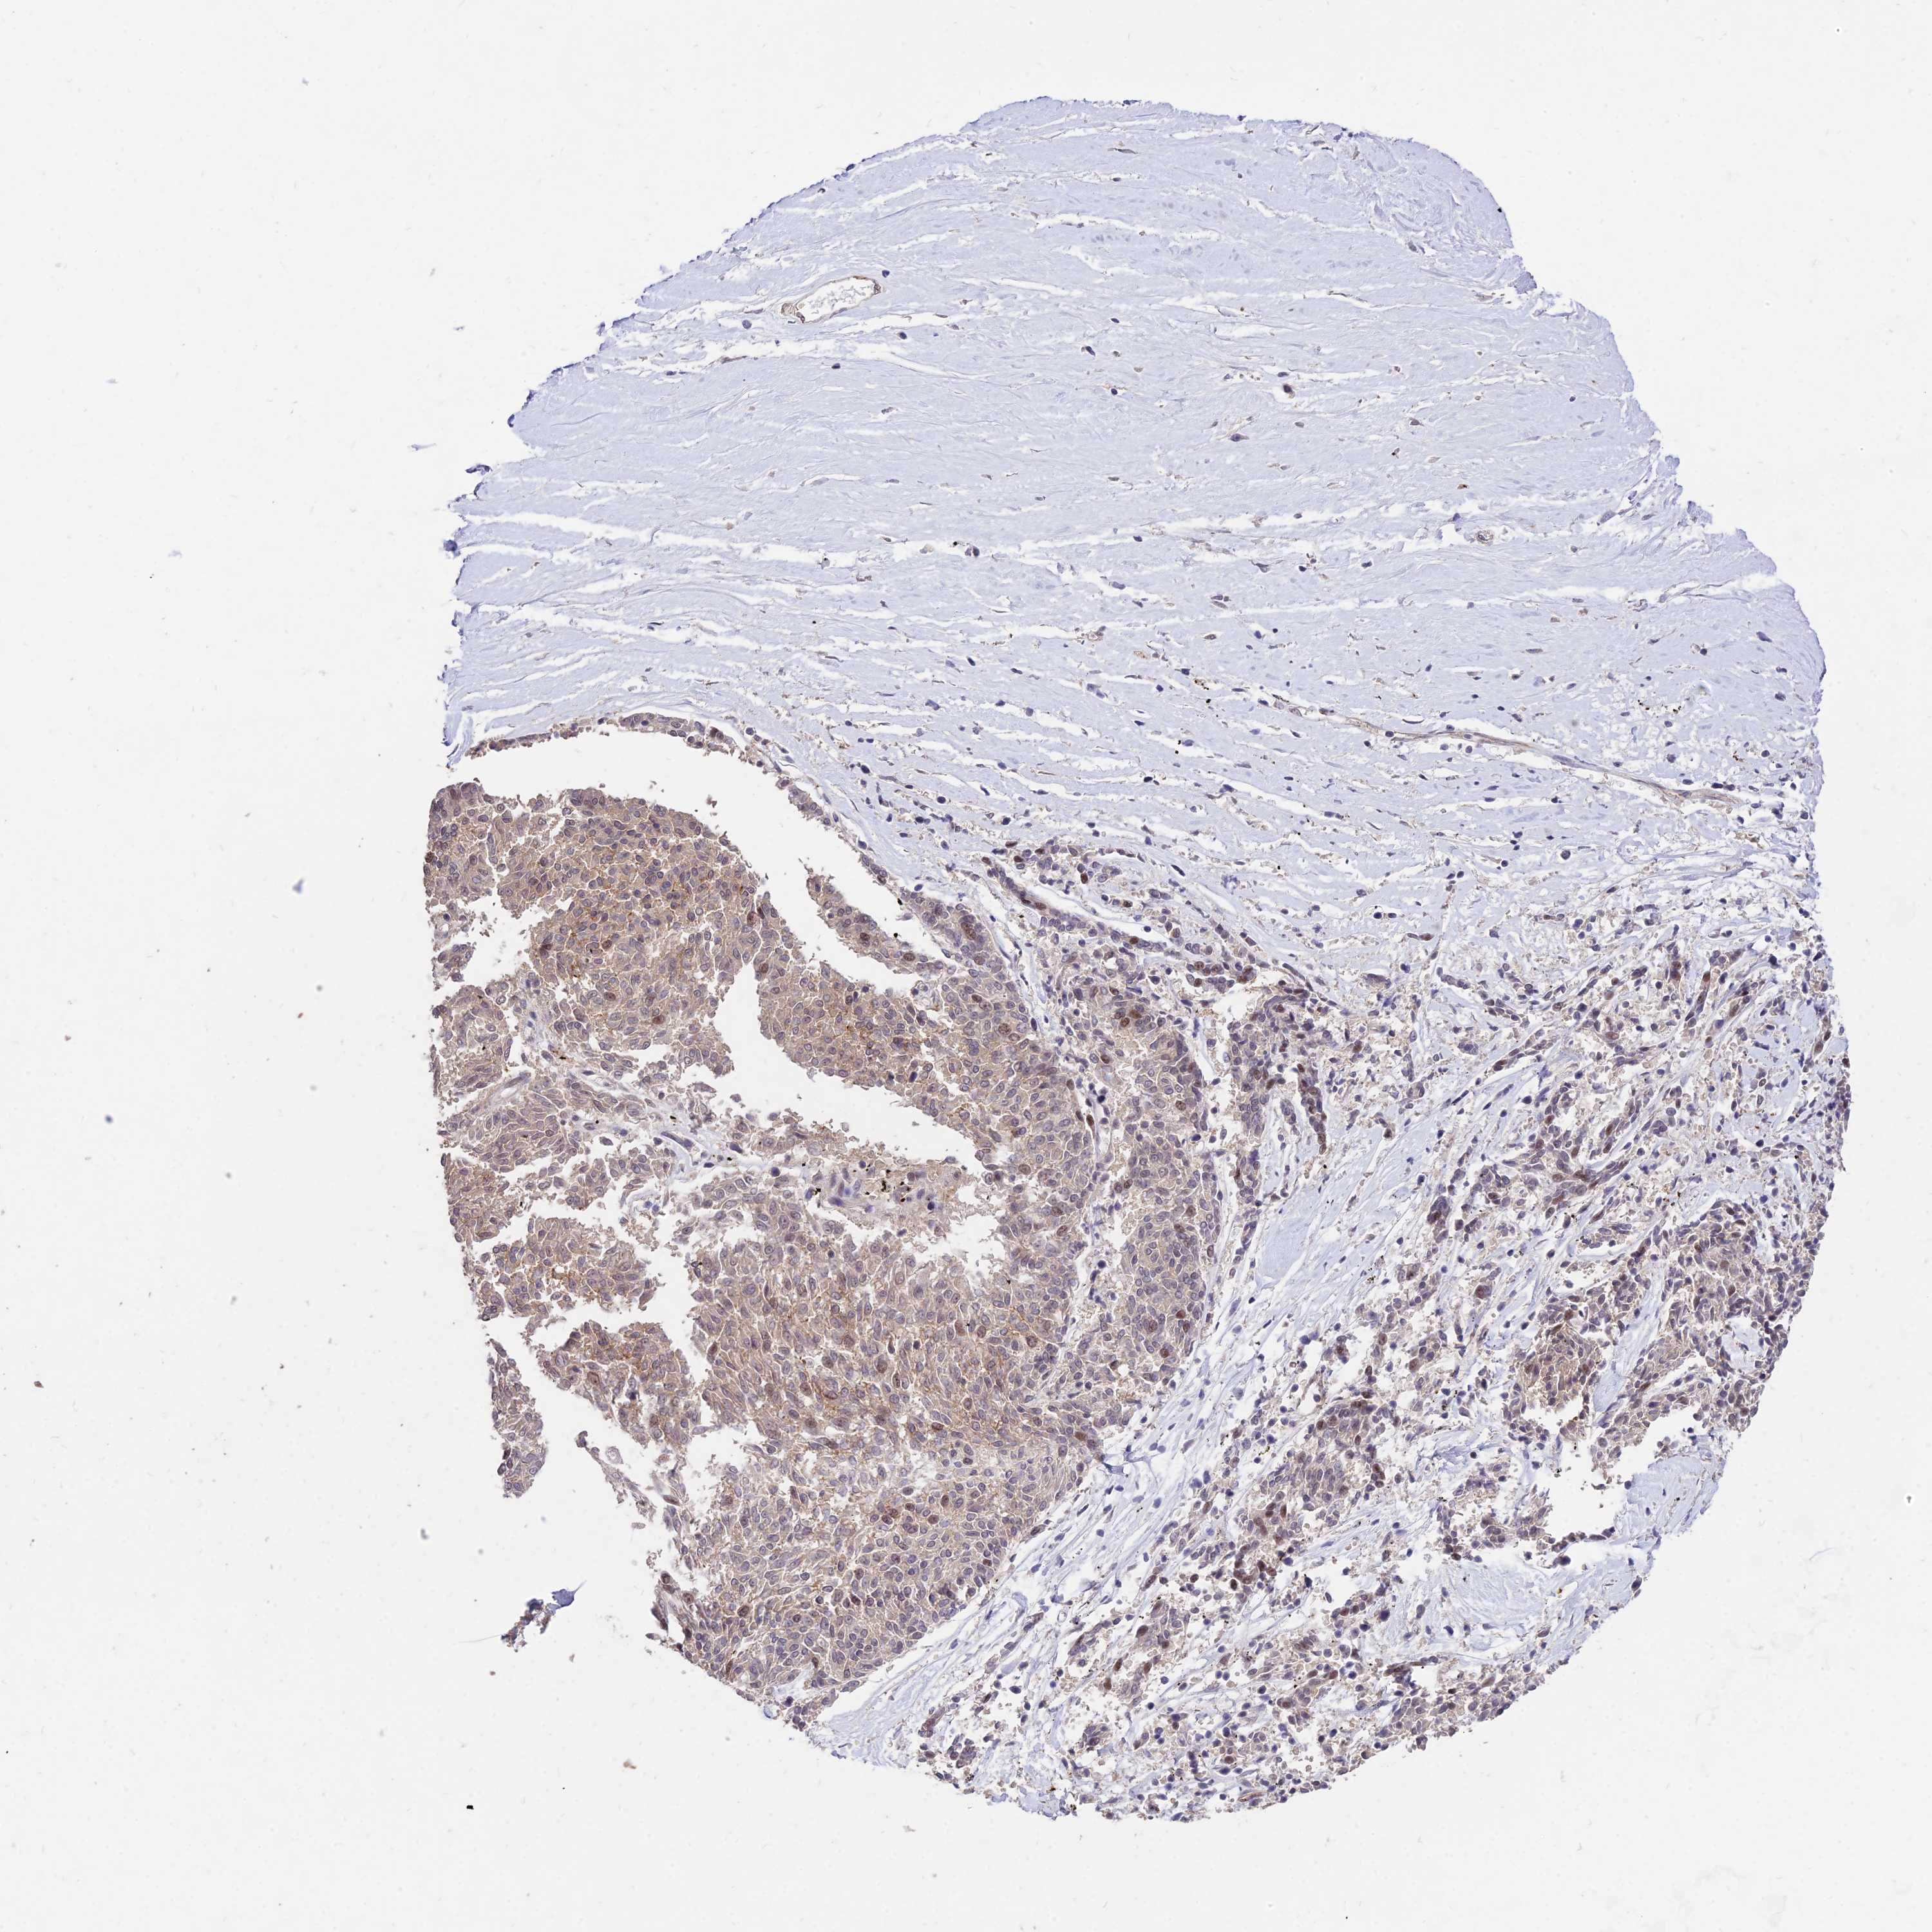

MELANOMA - Protein expressioni

A mouse-over function shows sample information and annotation data. Click on an image to view it in a full screen mode. Samples can be filtered based on level of antibody staining by selecting one or several of the following categories: high, medium, low and not detected. The assay and annotation is described here.

Note that samples used for immunohistochemistry by the Human Protein Atlas do not correspond to samples in the TCGA dataset.

Antibody stainingi

Antibody staining in the annotated cell types in the current human tissue is reported as not detected, low, medium, or high, based on conventional immunohistochemistry profiling in selected tissues. This score is based on the combination of the staining intensity and fraction of stained cells.

Each image is clickable and will lead to virtual microscopy that enables deeper exploration of all samples and also displays staining intensity scores, fraction scores and subcellular localization as well as patient and tissue information for each sample.

Antibody HPA044760

Staining

High

Medium

Low

Not detected

Intensity

Strong

Moderate

Weak

Negative

Quantity

>75%

75%-25%

<25%

None

Location

Nuclear

Cytoplasmic/membranous

Cytoplasmic/membranous,nuclear

Malignant melanoma, NOS

Malignant melanoma, Metastatic site